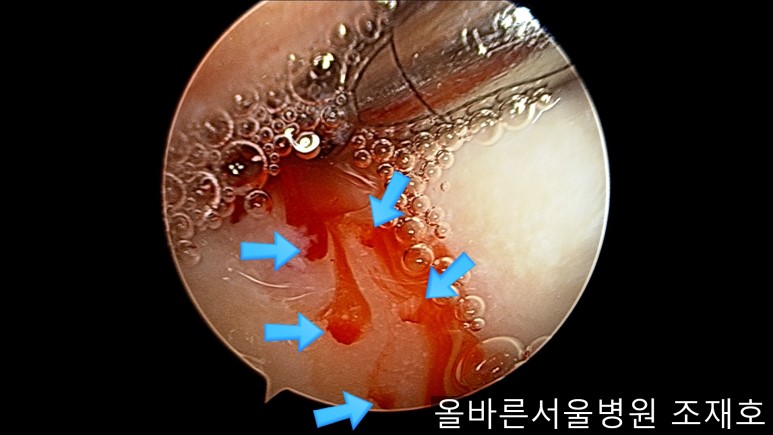

为了软骨再生,在胫骨上端进行微骨折术。

胫骨上端是通过微骨折术,可再生软骨的地方。

尽量将孔打地细密,确认此处骨髓腔内的血流出。

在股骨部位用CARTISTEM注射用4mm激光钻细密打孔,并确保软骨板不倒塌。不用切开通过关节镜即可完成手术。

如图,尽量细密打孔。